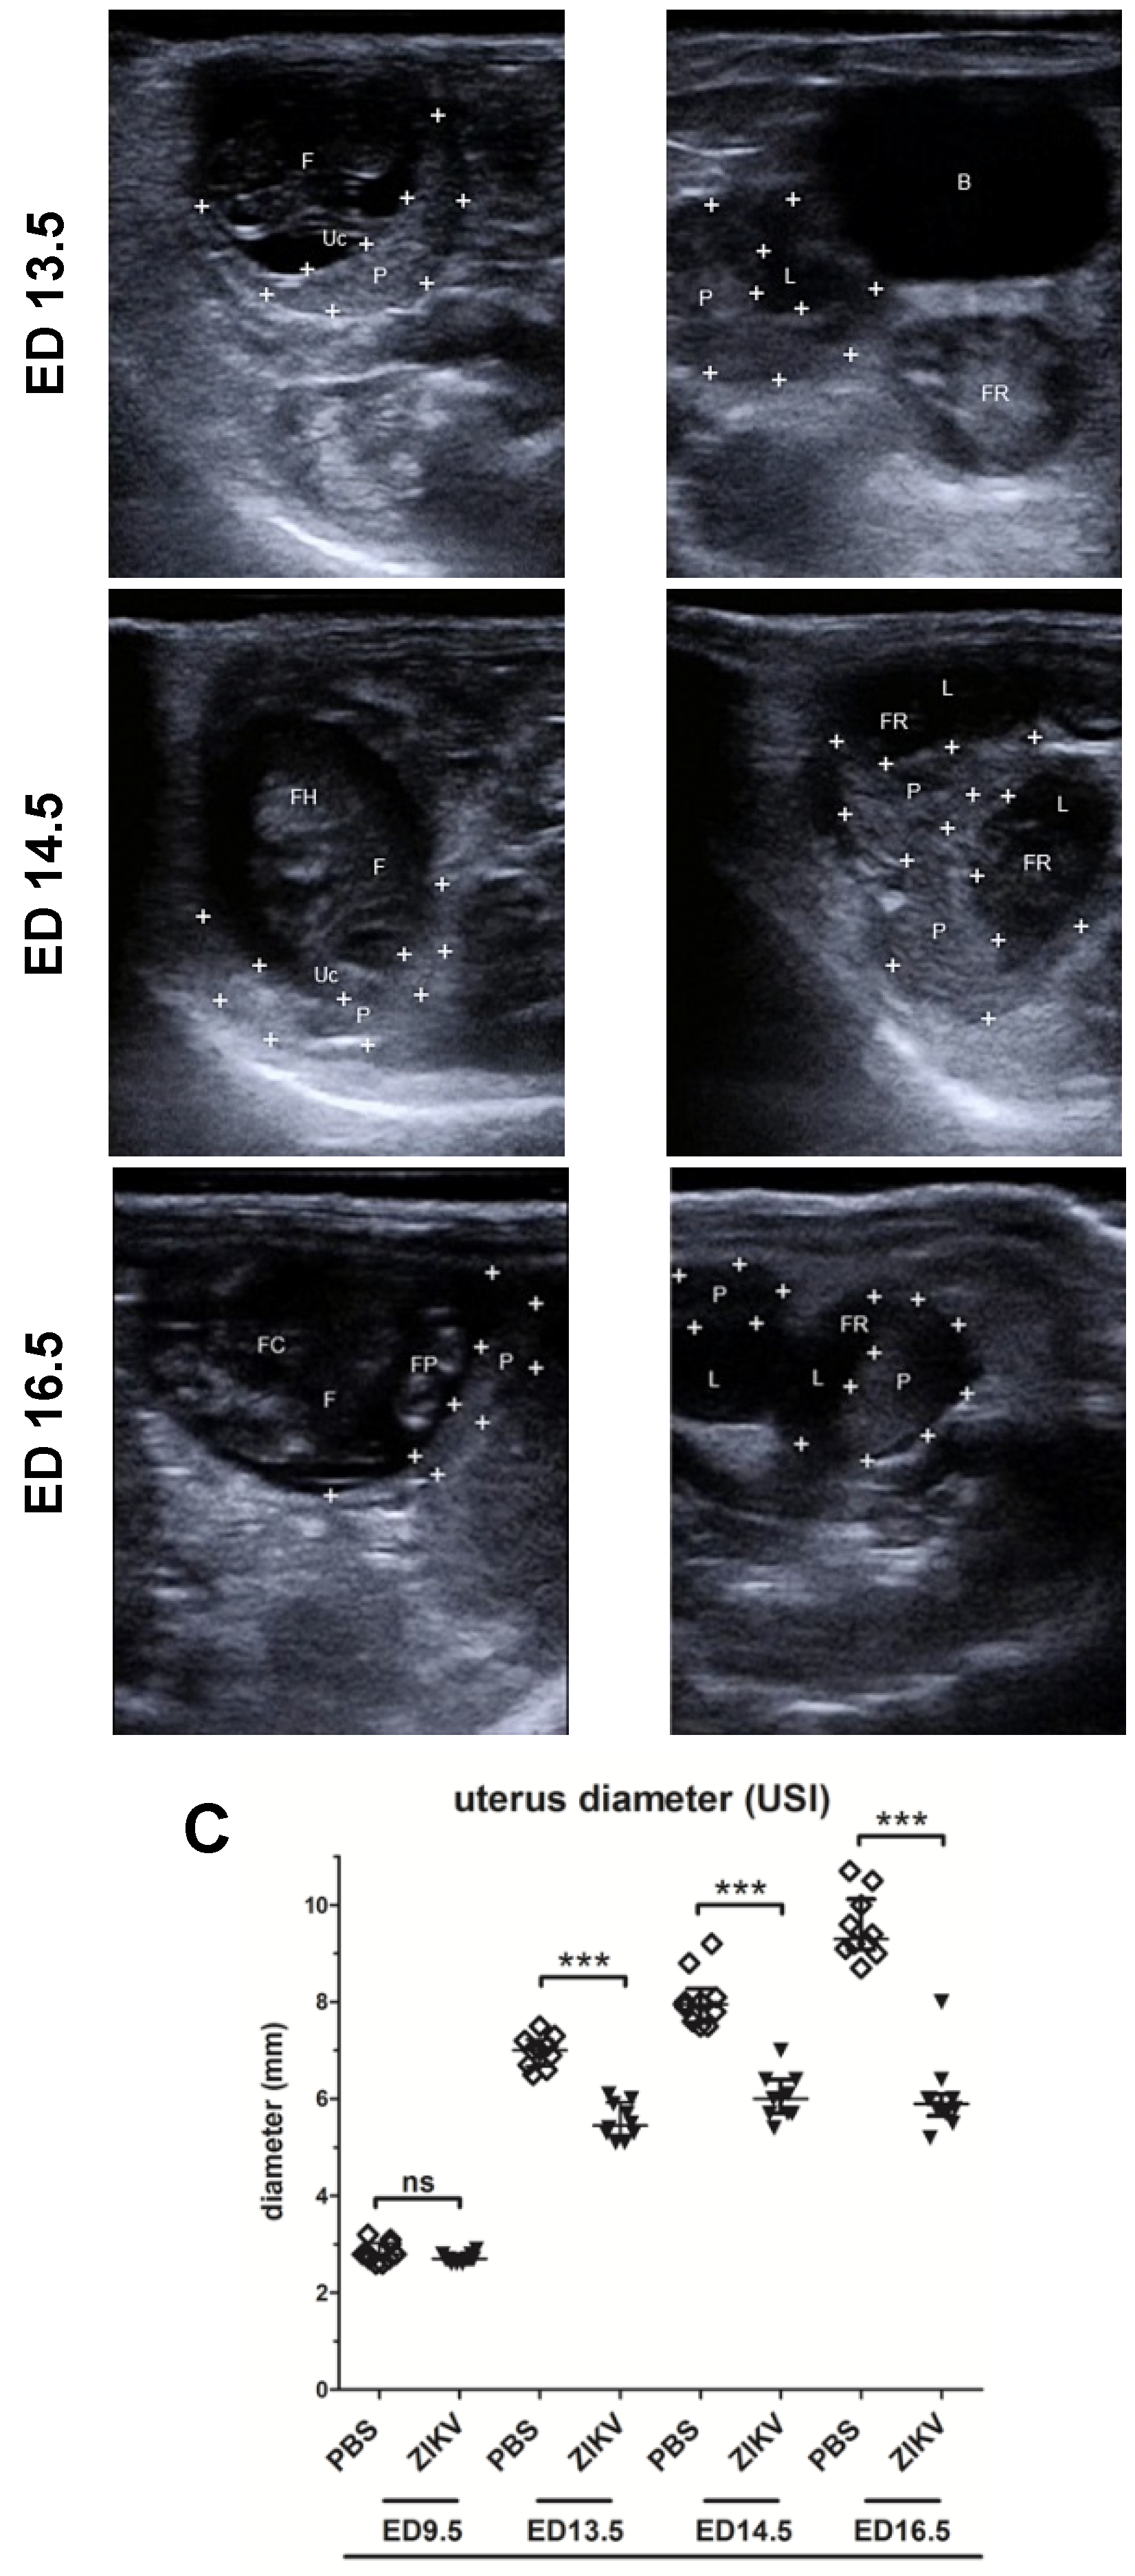

3.1. Outcome of ZIKV Infection in Pregnant IFNAR-/- Mice as Analyzed by Sonography

3.2. Evaluation of Uteroplacental Blood Flow Activity by Doppler Ultrasound